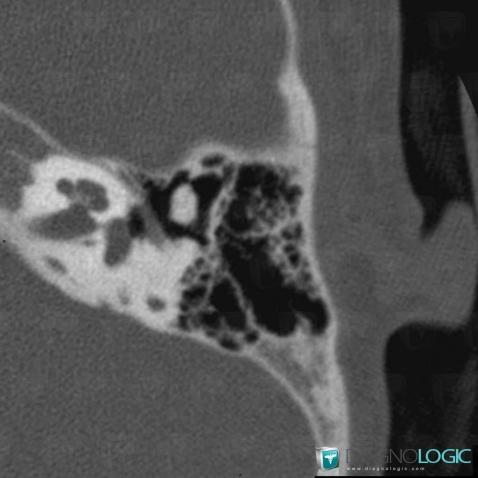

Major aplasia, Middle ear, CT

Here is the specific information in the key image above:

- Diagnosis Major aplasia, Location(s) Middle ear, with gamuts